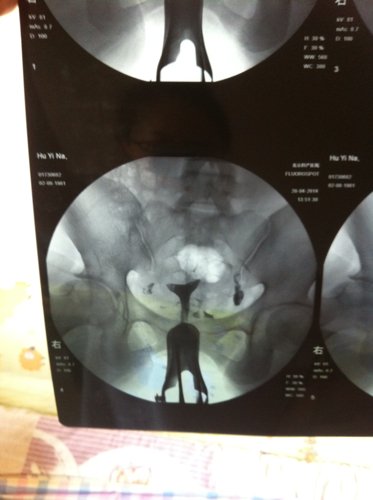

正规医院做的造影,左侧输卵管少许通畅,右侧阻塞,该怎么办呀 点击展开 匿名用户 2014-05-05 11:38 为您推荐: 其他回答 病情分析: 你好,你做造影检查一侧完全堵塞,另一侧通而不畅,这种情况需要在医生指导下及时治疗的。 指导意见: 建议先用中药治疗观察看看,如果效果不理想,可以考虑手术治疗。 夕菲菲_ci8W 2014-05-05 12:14 相关问题 我做的输卵管造影,右侧输卵管阻塞,左侧输卵管不全阻塞,请问你下大家,这种情况还能通开嘛?该怎么办? 性生活5年,男方精液常规检查无异常,女方输卵管造影无阻塞,有正常卵泡发育及排卵;宫颈粘液抗精子抗体 我去年做的输卵管造影,是正常的,现在去另一个医院,医生让我重新做,说过半年就得重新做,请问我有必要